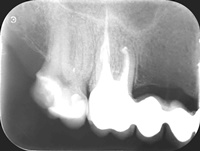

Pacjentka zgłosiła się z bólem. Ząb prawa dolna czwórka po leczeniu kanałowym. Nawracające dolegliwości bólowe, od kilku lat okresowo zaostrzające się. Podjęto decyzję o rewizji leczenia kanałowego. Udróżniono kanał korzeniowy, oraz odnaleziono kanał dodatkowy. Zdjęcie początkowe i zdjęcie po leczeniu endodontycznym pod mikroskopem.